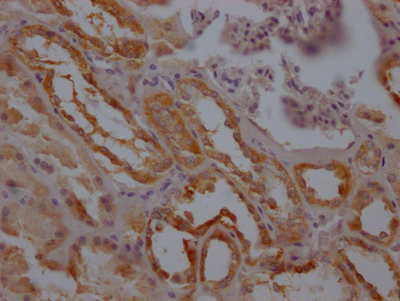

IHC image of CSB-RA776663A0HU diluted at 1:100 and staining in paraffin-embedded human kidney tissue performed on a Leica BondTM system. After dewaxing and hydration, antigen retrieval was mediated by high pressure in a citrate buffer (pH 6.0). Section was blocked with 10% normal goat serum 30min at RT. Then primary antibody (1% BSA) was incubated at 4℃ overnight. The primary is detected by a Goat anti-rabbit IgG polymer labeled by HRP and visualized using 0.05% DAB.